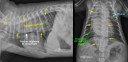

RadioQuiz 39 – Mégaoesophage avec pneumonie par aspiration, non ?

RadioQuiz 37 – Réponse

RadioQuiz 23 – Réponse